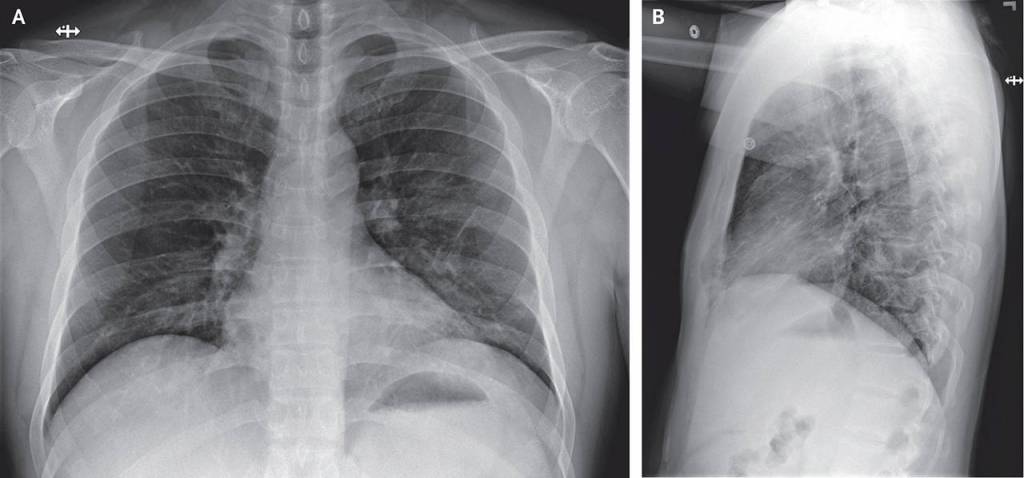

The article details the patient’s symptoms — everything from fatigue, nausea, diarrhea to a runny nose — over time and graphs his lab results. It shows X-rays of his lungs.